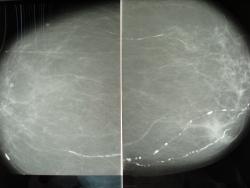

Профилактическая маммография, женщина 1946г.,жалоб нет. Выскажите мнение уважаемые коллеги, прошу прощение за качество снимков

Атеросклероз маммарных артерий на фоне тотальной инволюции. Встречается в той или иной степени примерно у 40% после 50 лет (по моим данным).

так то оно так, а что в левой молочной железе?

Справа мелкие исвестковые кисты, слева - локальный фиброзец.

При наличии микро кальцификатов рекомендуется пункционная биопсия

Категория  4 по классификации BIRADS (подозрительная)

При отсутствие  кальцификатов , асиметрическое локальное утолщение кожи в одной из 2-х пр.

- участок локального фиброза?

Категория 3 с провидением УЗД  и контроль 5- 6 мес.

При наличие маммографического рентген архива ( при отсутствие динамики0 кат 2 – контроль 1 год.

Поскольку видела немало печальных следствий такого "наблюдения", ответственно отвечаю,   при условии, что у пациентки в этой зоне нет послеоперационного рубца,  в данном случае: участок локального фиброза с перестройкой, конвергенцией фиброзной стромы, уплощением и уплотнением кожи, скоплениями микрокальцинатов в нижне-внутреннем квадранте; рентгенологическая картина крайне подозрительна на рак и, в любом случае, требует обязательного морфологического исследования. Наблюдательная тактика не верна!

Ну, а если начать анализировать "фрагмент", то необходимо полностью согласиться с Татьяной Валентиновной.

с вами согластна, пациентка была направлена в оод, онкологи не нашли показаний для узи и пункции, заключение онколога маммолога - неполная фиброзно- жировая инволюция

Что касается Финляндии, то я уже писала где-то здесь на сайте, недавно финны расказывали, как у них обстоят дела в маммологии. Так вот, при рентгенологических подозрениях на рак молочной железы, ВСЕГДА делается биопсия, прицельно берется 5-7 стобиков ткани из разных мест. При отрицательной биопсии,  случаи обсуждаются совместно с рентгенологом и клиницистом и зачастую делают резекцию подозрительного участка. Поэтому они и не видят опухоли больше 15мм.

узисты смотрели? узи покажит фиброз или инфильтрат если инфильтрат тогда биобсия